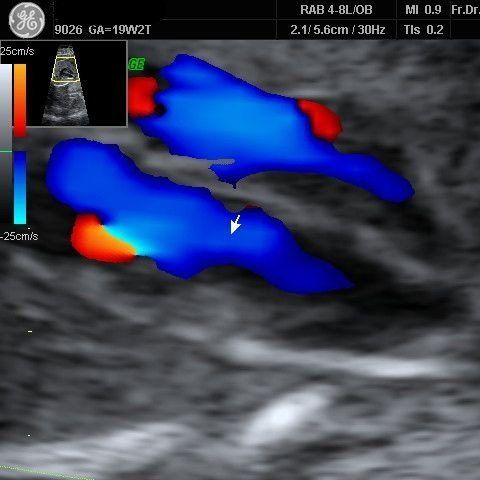

Untersuchung des kindlichen Herzens.Bei der fetalen Echokardiographie wird das Herz mittels hochauflösendem Ultraschall, einschließlich der zu- und abführenden Gefäße, untersucht.

Die Farb-Doppleruntersuchung kann helfen Gefäßfehlbildungen zu erkennen.